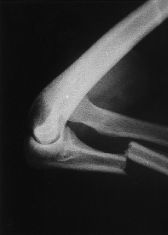

Mecanismo de lesion de esta fractura

Mecanismo DIRECTO

Golpe directo al codo por caida o trauma

Tipo de fractura en la clasificacion de Mayo

2a (Desplazada estable, no conminutada)

Tratamiento de esta fractura

Obenque con clavillos de kirschner y alambre